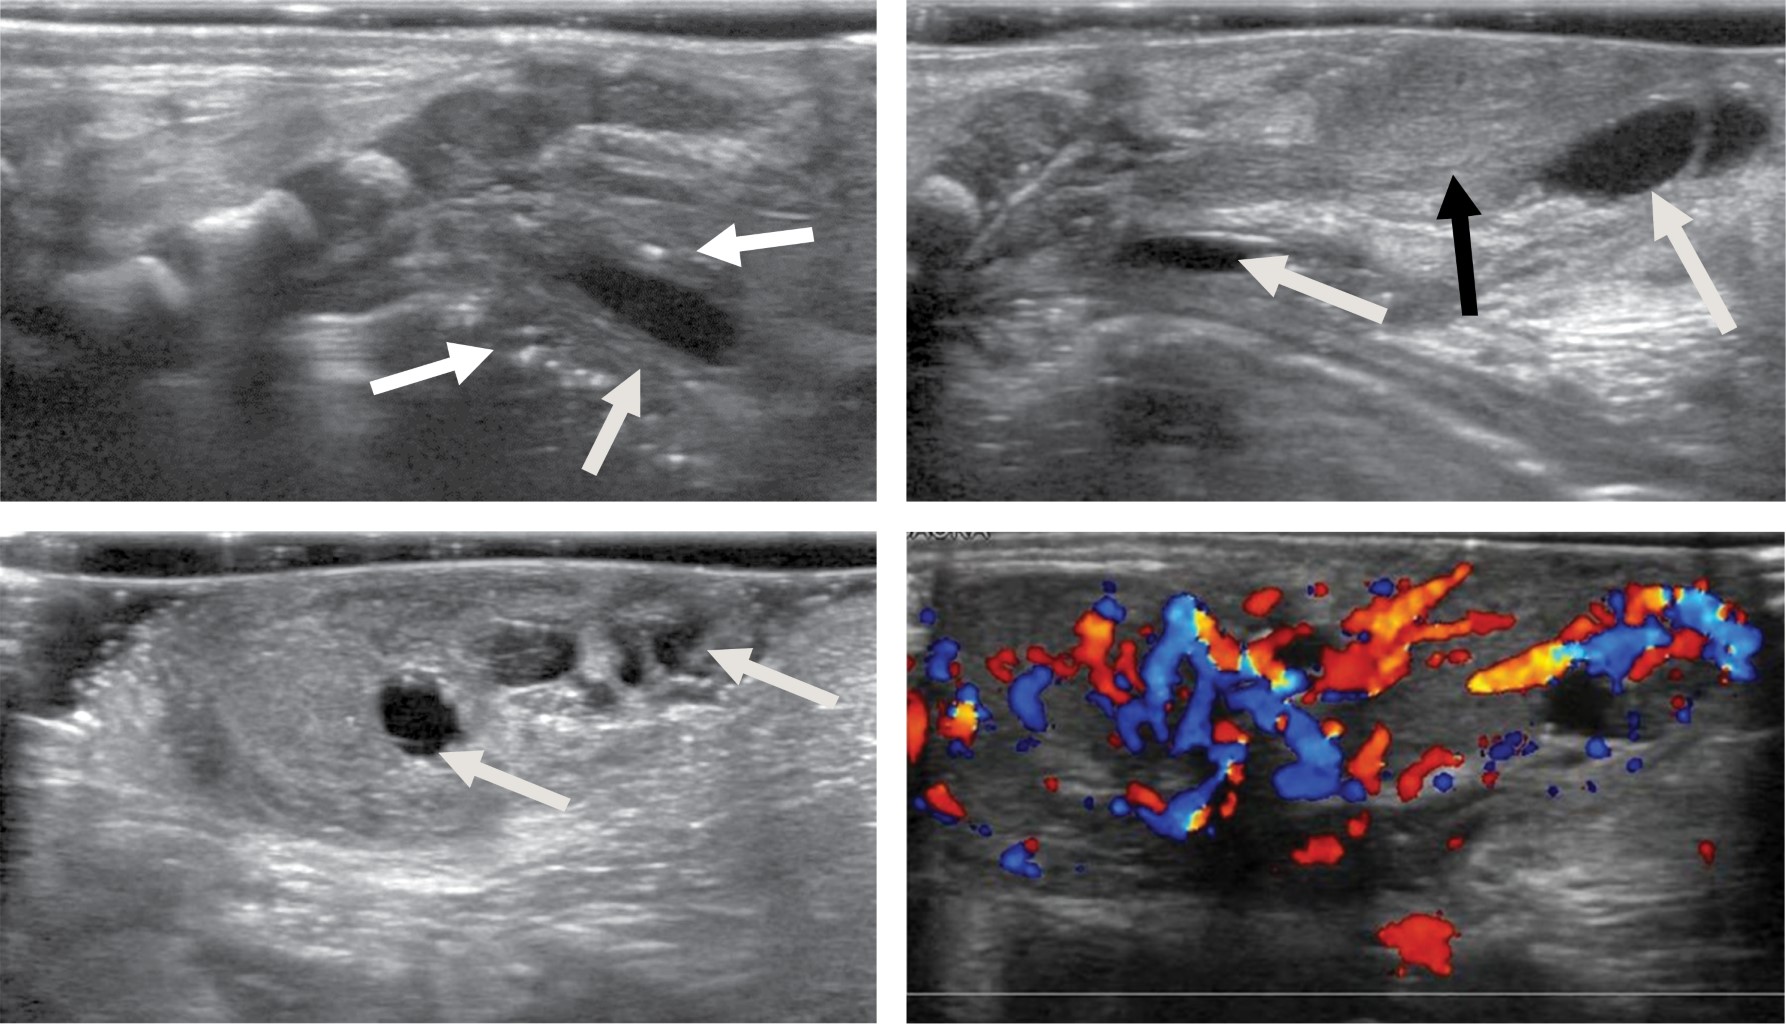

El abordaje diagnóstico imagenológico es esencial para demostrar la extensión intraabdominal y los efectos en las estructuras adyacentes. Los hallazgos por imagen del teratoma van acordes a sus componentes. Por radiografía se observará una masa de dimensiones variables que puede estar asociada a calcificaciones.10 El ultrasonido mostrará una masa de ecotextura heterogénea con presencia de focos ecogénicos de calcificaciones y grasa así como áreas quísticas anecoicas. El modo Doppler color demuestra que los componentes sólidos presentan vascularidad de moderada a alta.10,11 La tomografía computarizada muestra una masa con densidad heterogénea por sus componentes de grasa, calcio, tejidos blandos y niveles de líquido. El medio de contraste muestra un patrón de reforzamiento variable en los componentes sólidos. La resonancia magnética presenta hallazgos con intensidad de señal heterogénea. En T1 la grasa se aprecia hiperintensa, los tejidos blandos isointensos, el componente quístico hipointenso y el calcio marcadamente hiperintenso. En T2 se observa el componente quístico hiperintenso y el calcio marcadamente hipointenso. El T1 con contraste presenta un reforzamiento heterogéneo del componente sólido.3,10 Los hallazgos por imagen no pueden predecir subtipos histológicos de tumores, pero existen características de benignidad y malignidad. El componente quístico, las calcificaciones y el contenido graso prominente corresponden a hallazgos más comúnmente observados en lesiones benignas. La hemorragia y/o necrosis dentro de la masa, mayor componente sólido y realce heterogéneo con contraste son más sugestivos de malignidad.3,6 El diagnóstico prenatal se realiza con ultrasonido obstétrico y/o con resonancia magnética fetal, identificando una masa sacra heterogénea con componentes quísticos y sólidos.2,3 Postnatalmente la resonancia magnética permite la diferenciación de tejidos, extensión intramedular y pélvica, siendo superior a la tomografía computarizada al no exponer a una dosis de radiación ionizante.12 Se debe realizar diagnóstico diferencial principalmente con mielomeningocele, lipomas, hemangiomas, quiste pilonidal y epidermoide.2,7 El neonato puede presentar complicaciones cardiacas, anemia e hidrops fetal. Durante el parto puede ocurrir ruptura del teratoma y hemorragia al ser altamente vascular. Si es suficientemente grande puede ocasionar efecto de masa en estructuras adyacentes.2,3,13 El tratamiento es principalmente quirúrgico, ya sea prenatal o postnatal. La cirugía fetal intrauterina es una opción en fetos de alto riesgo como los productos con hidrops fetal. Postnatalmente la resección quirúrgica temprana se realiza para evitar progresión a malignidad y recurrencias. Los pacientes con teratoma maligno requieren manejo combinado de cirugía, quimioterapia y radiación.3,14

Paciente femenino de 32 años de edad sin antecedentes de importancia. Tomó ácido fólico previo al embarazo. Gesta dos, cesárea uno. Su primera consulta del embarazo actual fue a las 7.2 semanas de gestación (SDG) con longitud cráneo caudal acorde a la edad gestacional estimada por fecha de última menstruación. En la semana 12 se realizó ultrasonido estructural donde se observó aparente defecto a nivel sacro que parecía tener continuidad con médula espinal. En el ultrasonido a la semana 16 se apreció una imagen de contenido anecoico en la región sacra y con aparente continuidad al canal medular, en probable relación con mielomeningocele (Figura 1). En la semana 20 se realizó amniocentesis y posteriormente microarreglos encontrando complemento cromosómico 46 XX, sin alteraciones en las regiones analizadas. Se realizó tamiz de glucosa y curva de tolerancia a la glucosa en la semana 27 diagnosticando diabetes gestacional, sólo requirió manejo dietético. En la semana 26 se realizó ultrasonido identificando en región glútea una imagen con ecotextura heterogénea de predominio anecoico, con medidas aproximadas de 3.3 × 3.2 cm, que no comprometía genitales y parecía corresponder a un teratoma sacro. Se realizan seguimientos ultrasonográficos con Doppler fetal y pruebas de bienestar fetal hasta el término. A las 38.2 SDG nace por cesárea producto femenino con peso de 2,669 g y talla de 48 cm. Llora y respira al nacer, se dan maniobras básicas de reanimación. Se califica con APGAR 9/9 y Silverman Anderson de 0. Ingresa a terapia intermedia. En la exploración física neurológicamente no mostró alteraciones, la fuerza y sensibilidad de las extremidades estaba conservada, sin movimientos anormales. En la región sacra se identificó una masa con tamaño aproximado de 2 × 2.5 cm que presentó sangrado en capa, la cual de forma atípica no tenía una cobertura de piel (Figura 2). Se realizó radiografía de pelvis, ultrasonido abdominal, transfontanelar y de región sacra. Se tomó radiografía anteroposterior y lateral de pelvis que reveló integridad de los cuerpos sacros y los elementos del arco posterior sin alteraciones aparentes así como una masa con densidad de tejidos blandos inferior a la región del sacro (Figura 3). En el ultrasonido abdominal no se reportaron alteraciones, se valoró la vejiga y riñones, mismos que mostraron situación, morfología y ecogenicidad normales. El ultrasonido transfontanelar no mostró anomalías. Se realizó rastreo con transductor lineal multifrecuencia en escala de grises y con modo Doppler color de la columna lumbosacra (Figura 4). Se decidió realizar resonancia magnética para mejor caracterización de la extensión de la masa descrita. Se efectuaron secuencias multiplanares de la columna lumbosacra y panorámica sagital de la columna completa (Figura 5). Se realiza la resección completa de la tumoración, respetando estructuras pélvicas y lográndose una cobertura completa sin tensión de la herida. Adecuada recuperación postoperatoria, por dehiscencia parcial de herida se maneja sistema VAC ambulatorio, el cual es una terapia no invasiva que utiliza presión negativa sobre la herida para ayudar a la cicatrización en un medio húmedo y cerrado, lo que favorece la angiogénesis, el tejido de granulación y disminuye la colonización bacteriana (Figura 6). Niveles séricos de alfa fetoproteína y fracción beta de gonadotropina coriónica preoperatorios normales. El reporte de patología reveló teratoma inmaduro (elementos inmaduros menores de 1%), superficie externa con piel ulcerada. Después de un año de vigilancia, no hay datos de recidiva clínica o por laboratorio.

La caracterización por imagen clásica del teratoma consiste en una masa heterogénea, que por su origen embriológico (tres capas germinales), presenta componentes sólidos y quísticos, con áreas de tejido graso y áreas de calcificación,1-3 los cuales se demostraron en nuestro caso mediante el ultrasonido y la resonancia magnética.

Es importante hacer el diagnóstico diferencial con el mielomeningocele, lipomas, hemangiomas, quiste pilonidal y epidermoide.3 Éstos tienen una localización posterior al sacro. El teratoma sacrococcígeo tiene una localización entre el coxis y el ano y tiende a estar recubierto por piel.2 Asimismo, se debe evaluar la médula espinal, dado que el mielomeningocele tiene afectación asociada de la misma.11 En este caso se constató la integridad de los cuerpos sacros y del arco posterior así como del canal medular mediante la valoración con radiografías, ultrasonido y resonancia magnética.